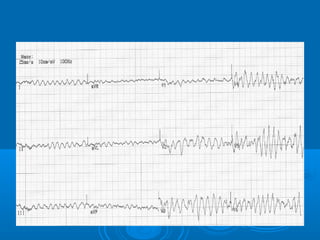

38 y M with CP

67y F HD CP at 0400am

65 y M with 1h CP

45y M CP for 13 h vitals stable

59 y F with 5h CP

56 y M with 3h CP

45 y M with 3h CP

62 y F with 45 min CP

59 y F 4h CP and BP 65/40

63 y F 5h CP BP 64/32